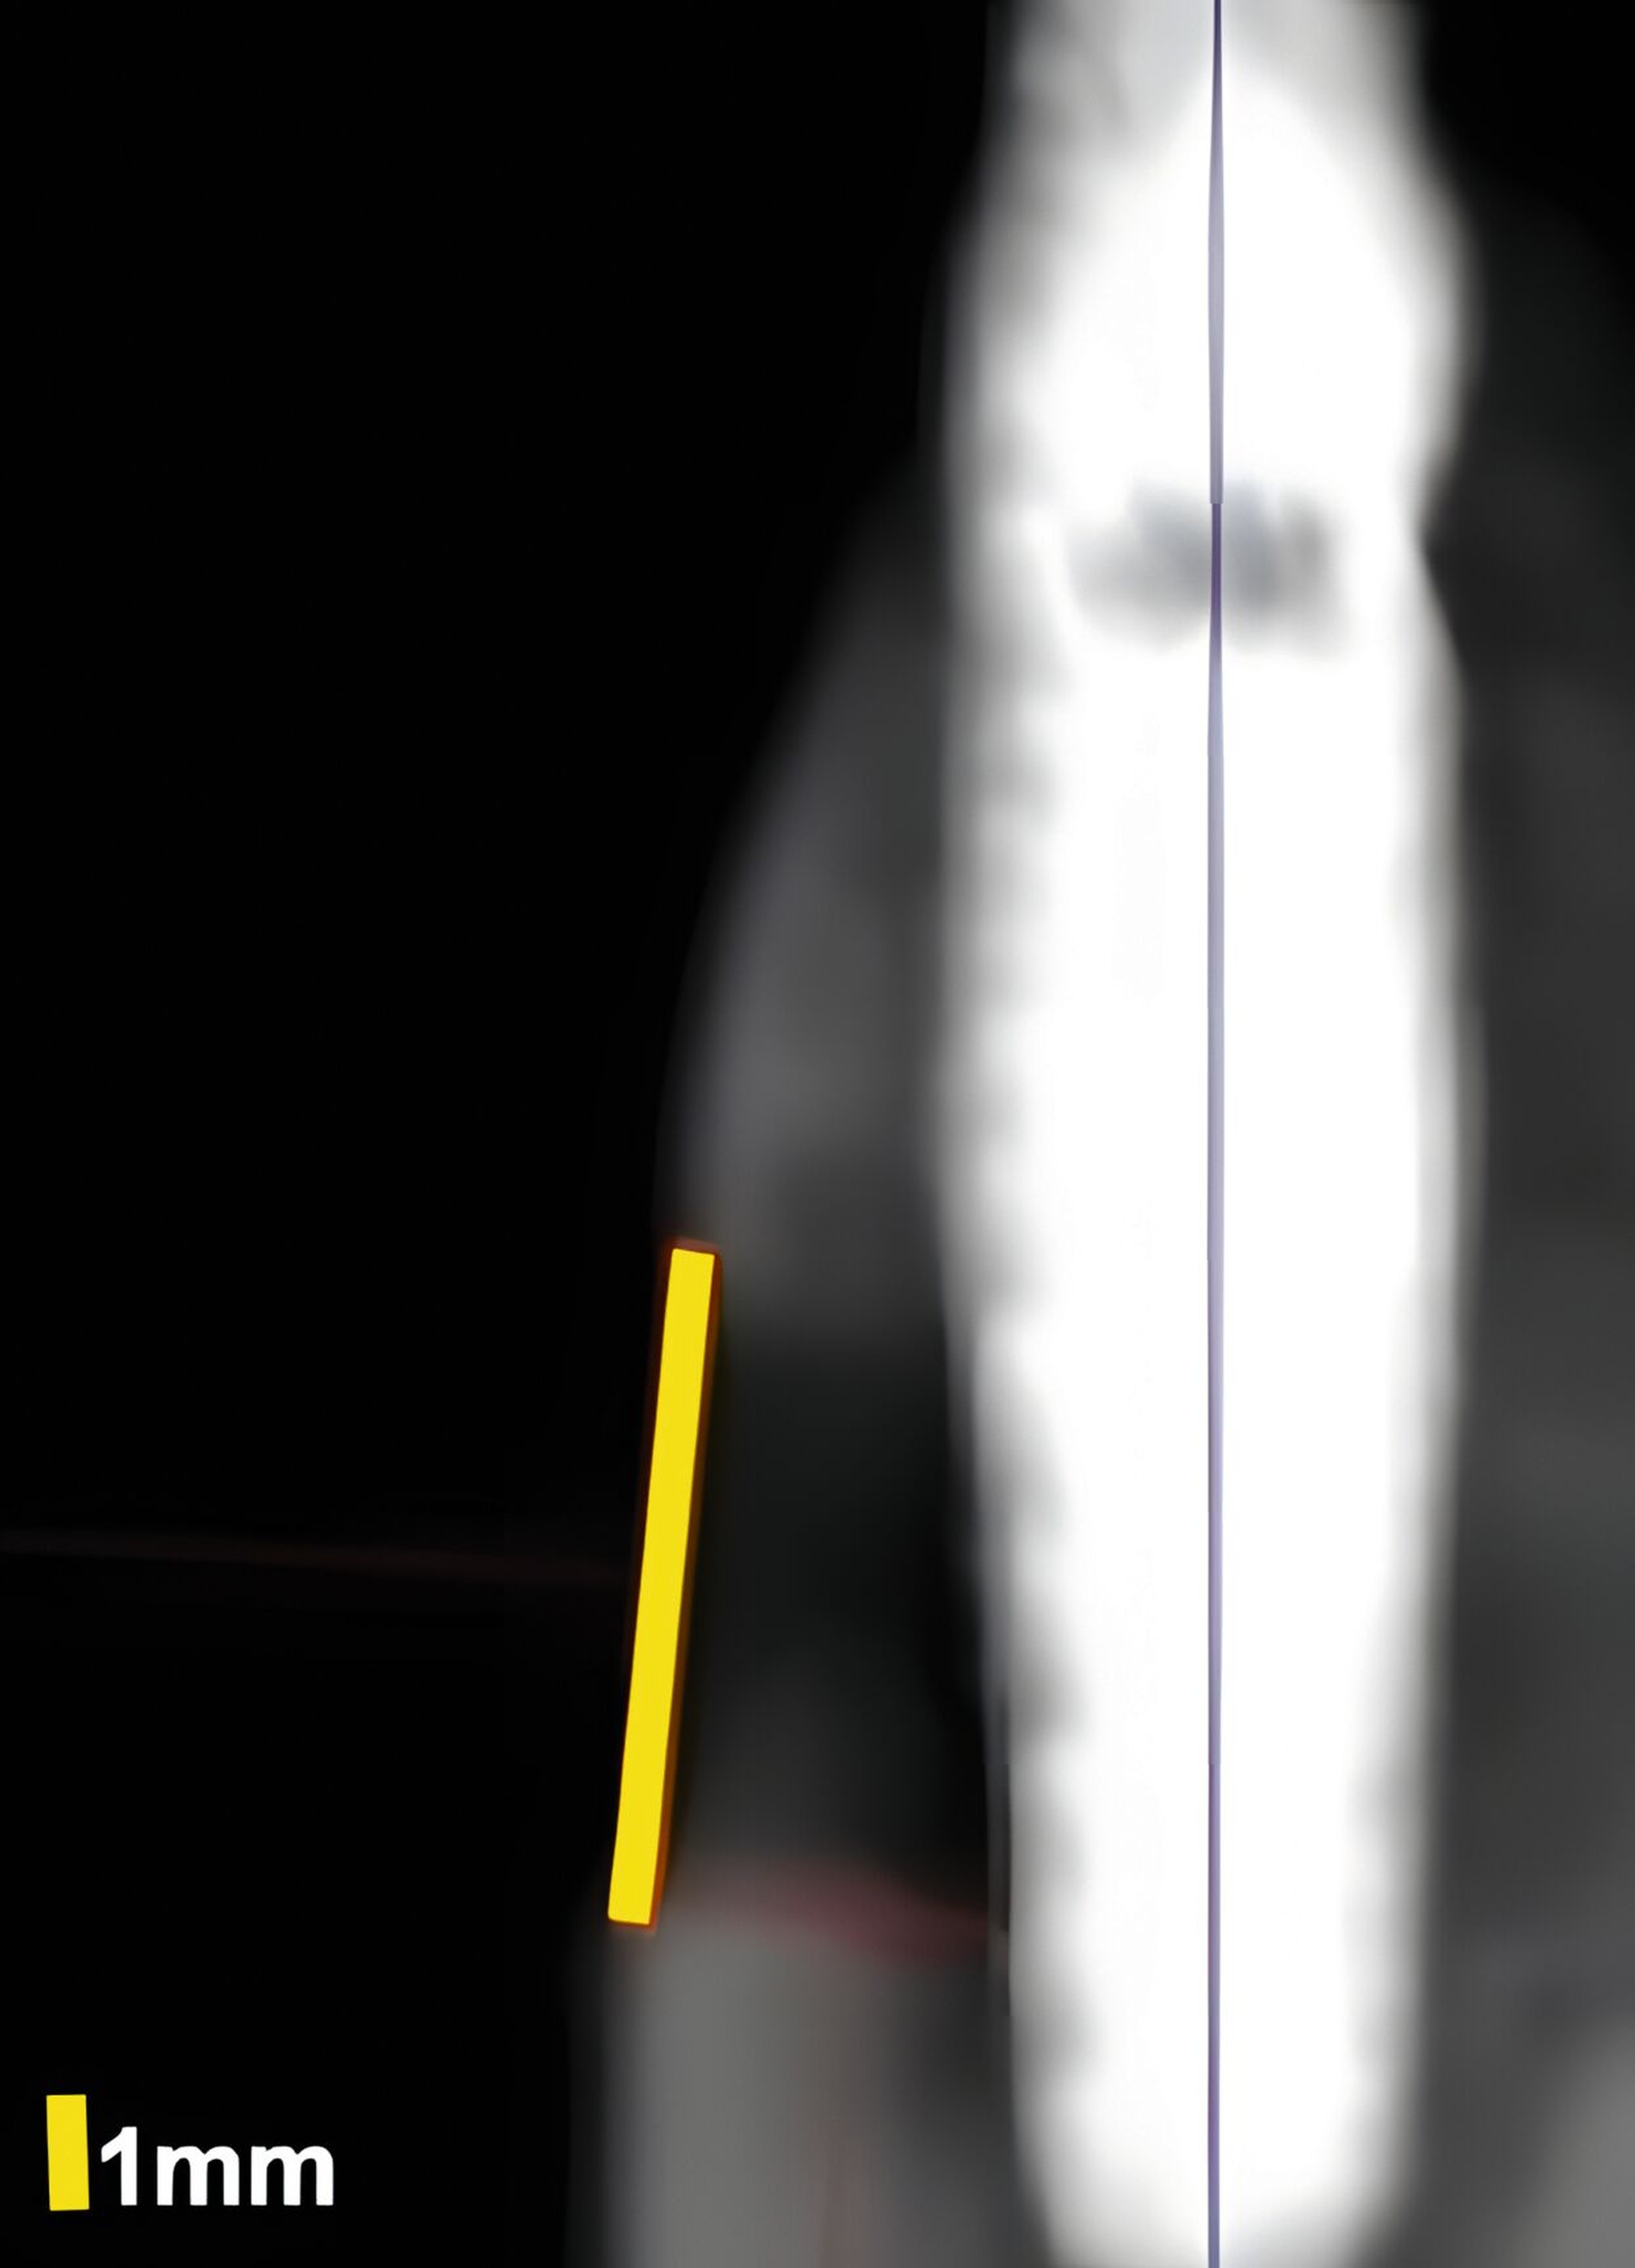

Dies konnte in einer ebenfalls eigenen humanen Kadaverstudie bestätigt werden [Bykhovsky et al., 2024]. Dabei wurden an Implantaten standardisiert Fenestrationen (n = 7), Dehiszenzen (n = 14) und dreiwandige Knochendefekte (n = 6) präpariert (Abbildungen 6 bis 8). Die Defekte wurden mit US- und DVT-Aufnahmen untersucht und die Messungen mit den direkten Messungen verglichen. Die US-Messungen zeigten eine starke Korrelation mit den direkten und den DVT-Messungen. Die sonografische Messgenauigkeit war bei Dehiszenzen am höchsten, gefolgt von Fenestrationen und dreiwandigen Knochendefekten.